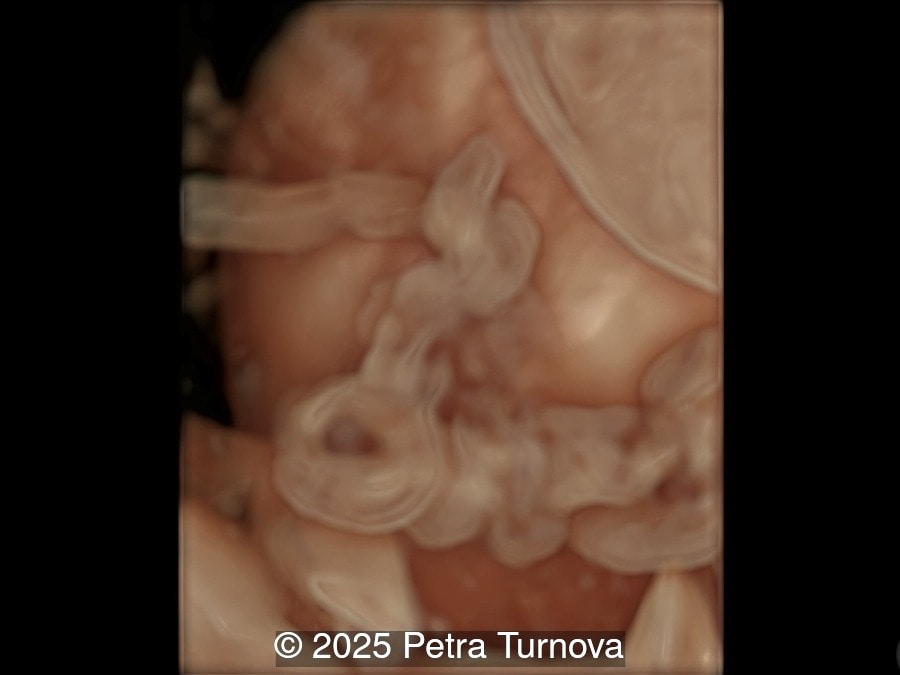

We present a case of cord entanglement. Unfortunately, the pregnancy ended in fetal demise two weeks after our exam.

Our images revealed a monochorionic monoamniotic pregnancy with entanglement of the umbilical cords. Simultaneous doppler registrations of two different heart rates suggests the cord entanglement.  There was no umbilical artery notching to suggest compromised blood flow to the fetuses.  Three-dimensional reconstructions of the umbilical cord entanglement is depicted in the images below.

Cord entanglement can be visualized from the 12-13 weeks of pregnancy. The risk of cord events increases in cases of close cord insertion on the placenta. Some studies have confirmed that intermittent occlusion is associated with neurological morbidity, while prolonged occlusion is fatal. Ultrasound may visualize intertwined umbilical cords. On Doppler flow studies, intermittent or persistent notching of the umbilical artery may be present. This phenomenon is typically observed in abnormal uterine artery flow associated with placental insufficiency and is less frequently seen in umbilical artery flow disorders. Based on physical calculations, it has been shown that notching does not occur unless there is a reduction in tube diameter below 75%. Therefore, notching is present in cases of significant flow reduction.